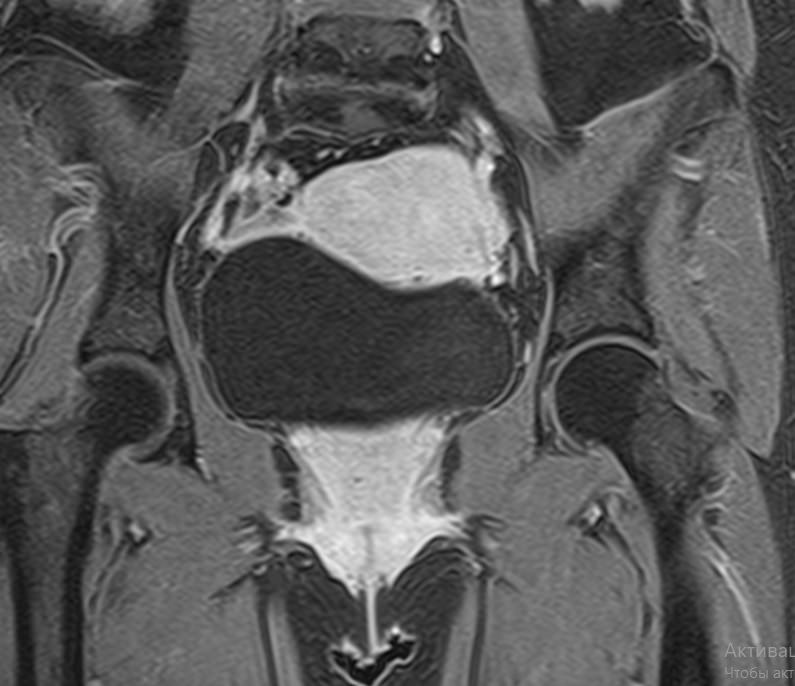

Магнитно-резонансная томография органов малого таза включает в себя исследование женских половых органов (матка, яичники), мужских половых органов (предстательная железа, семенные пузырьки, семявыносящие протоки), мочевого пузыря с мочеточниками, прямой кишки, тазовой брюшины, лимфатических узлов, мягких тканей малого таза.

В нашей клинике исследование выполняется на современном высокопольном томографе экспертного класса TOSHIBA VANTAGE TITAN 1,5 Тесла. Высокая индукция магнитного поля обеспечивает повышенную четкость изображений и превосходную детализацию анатомических структур. Аппарат производит сканирование в трех взаимоперпендикулярных плоскостях и послойными срезами с шагом от 1 мм, что позволяет визуализировать структуру органов и тканей малого таза в мельчайших подробностях.

Инновационные компьютерные программы преобразуют данные, полученные при сканировании, в 3D-изображения исследуемых органов. Методика трехмерной реконструкции используется для улучшения наглядности изображения зоны исследования, тем самым, повышает достоверность диагностики.

Выполнение МРТ малого таза в стандартном режиме возможно без использования контраста. Однако при подозрении на патологические изменения со стороны органов мужской или женской половой сферы, мочевыделительной системы, прямой кишки или окружающих мягких тканей, обязательным является введение контрастного препарата, имеющего в своем составе металл гадолиний. Степень и характер накопления контрастного препарата в органах и тканях позволяет различать патологические процессы, в том числе, диагностировать опухоли. Это используется для диагностики онкологических заболеваний на ранних стадиях, что имеет решающее значение для жизни и здоровья пациента.